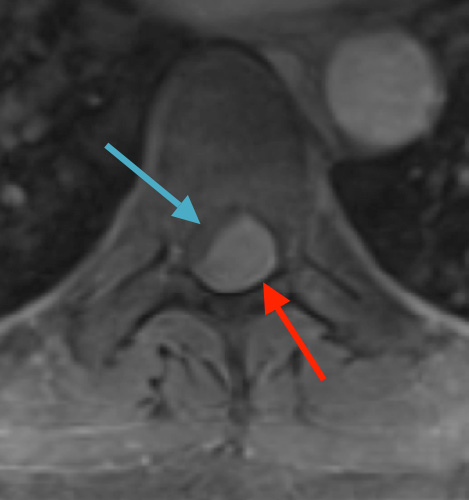

Preoperative MRI T2 demonstrating obstruction of CSF around the cord (blue arrow), resulting from the tumor (red arrow)

Postoperative MRI T2 illustrating the restoration of CSF surrounding the cord (blue arrow)